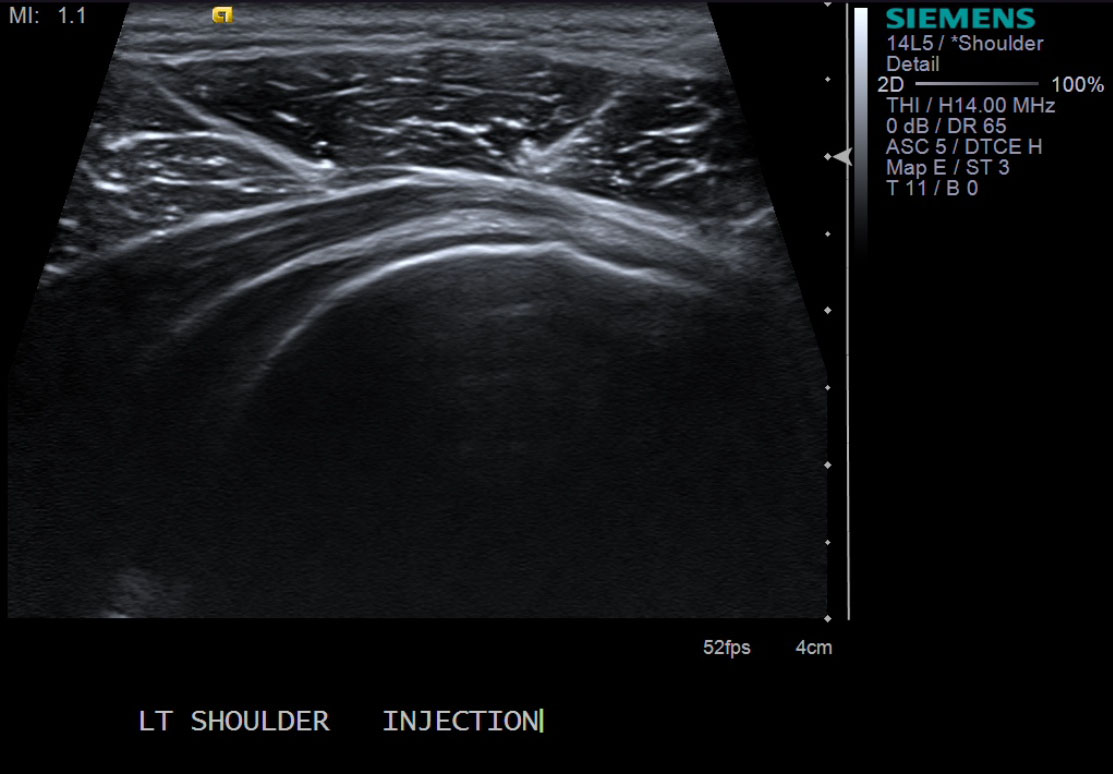

3. Scan patient looking for the posterior glenohumeral joint space. Image at the level of the infraspinatus tendon insertion in longitudinal orientation. Position probe so you can inject from anterior.

13. Document distention of the posterior joint recess with ultrasound.

• descriptiondescription